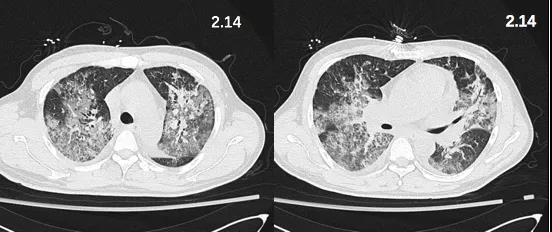

2月14日胸部CT复查提示双肺弥漫性渗出改变(图3)。

图3. 2月14日胸部CT

患者2月24日体温再次升高,而同期复查胸部CT较前明显好转(图4,5)。

图5. 2月25日胸部CT